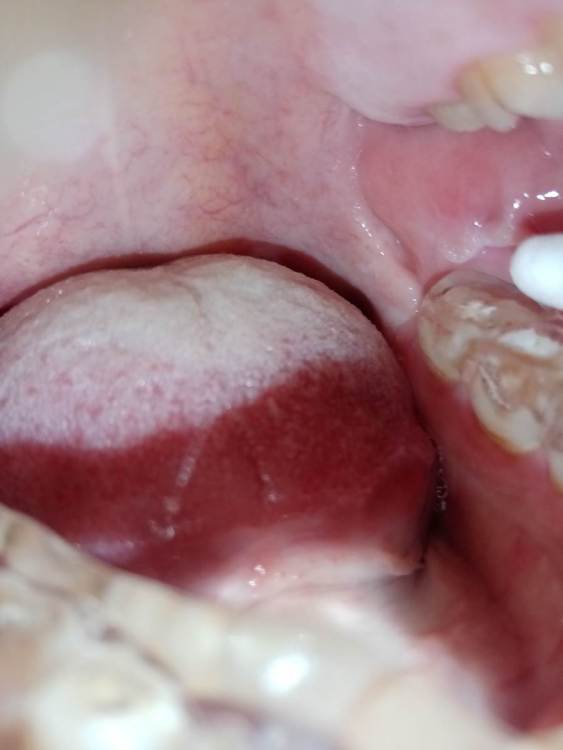

СмирноваД Опубликовано 29 июня, 2023 Поделиться Опубликовано 29 июня, 2023 Уважаемые стоматологи. Прошу Вашей помощи в поиске проблемы. Зуб удалили 2 года назад, но покоя там слизистая не дает. Болит, Разговаривать не дает вообще. Как буд-то там все пришили, и щеку и тяж со стороны горла. Какая-то шишка растет в конце верхней челюсти и как-будто давит там. Срослось оно вот таким образом "V"(со слов врача). Дергает щеку сильно , как-будто она прям пытается оторваться оттуда. и при наклоне головы прям в это место отдает. Со стороны горла тяж пришитый прям лоскутом к челюсти со стороны языка, трется об язык и тянет так сильно, что не дает разговаривать вообще, больно любые напряжения(разговаривать, глотать, пить,смеяться, и т.д.) прям чувствую как оно там все двигается, как нахождении чего-то инородного. Постоянно там все полощу, держу воду, потому что жжёт сильно. И доходит до рвотного рефлекса. Со стороны щеки,за зубом 4.7 корман. Пища попадает , и вытащить ее проблематично. Постоянно ощущение воспаления и лазию туда языком отодвигаю этот тяж, засовываю туда ватный диск, что бы просто снять напряжение и в этот момент могут быть такие жутки спазмы, что замираешь от боли. До трясучки и панических атак уже. Прикусываю там все, при чом даже с шиной (сплинт), щека лезет между зубов, приходится щеку вытаскивать.Шину ношу уже 10 месяцев, а толку нет. Рефлекторно, стараешься не двигать просто правой стороной вообще. Гнатолог , который делал шину, сказал, что нужно убирать рубцы, они все тянут. Но когда дошло дело до хирурга, хирург развел руками и сказал жить так, т.к. он ни чего сделать не может. Мало того у меня проблемы с суставом. а из-за этого напряжения на столько хуже, что к вечеру ни то что бы разговаривать, я и глотать слюну не могу. Сустав у меня теперь болит постоянно от напряжения, жуткие спазмы по всей голове, челюсти, до горла болит, с переходом на шею. При чом все врачи видят эти рубцы, что все прикусываю, трогают и мне больно, но говорят все по разному : один- надо искать, другой - там воспаление, третий- прикус, четвертый -как вы себе представляете это, это нужно было убирать сразу, пятый-сустав. Просто как идти к ортодонту с такими болями? И так же искала врача по пластике, но безрезультатно. На кт и снимках нет ни чего. Помогите, пожалуйста, хоть как-то разобраться. 230310_183333.rar Ссылка на комментарий

СмирноваД Опубликовано 11 августа, 2023 Автор Поделиться Опубликовано 11 августа, 2023 27.07.2023 в 19:43, annda сказал: Нельзя на ортодонтию идти в таком состоянии. Начните с банальной рутинной ежедневной самокоррекции хотя бы-пилатес,йога, Фельденкрайз и прочие подобные штуки. Единственные рубцы,которые у вас есть-это «линия Альба»,,следы прикусывания щек зубами.К месту удаления это не имеет никакого отношения, а к бруксизму -самое прямое. Извинете, Вы, не правы!Линия альбы! Тут ни какого отношения не имеет. Я не могу сфотографировать как выглядет вся слизистая за 4.7. зубом. Ссылка на комментарий

Bier Опубликовано 16 августа, 2023 Поделиться Опубликовано 16 августа, 2023 я вижу рубец на щеке, вы накусали его, ну если он мешает можно его отрезать. Но по источнику боли соглашусь с Анной. Ссылка на комментарий